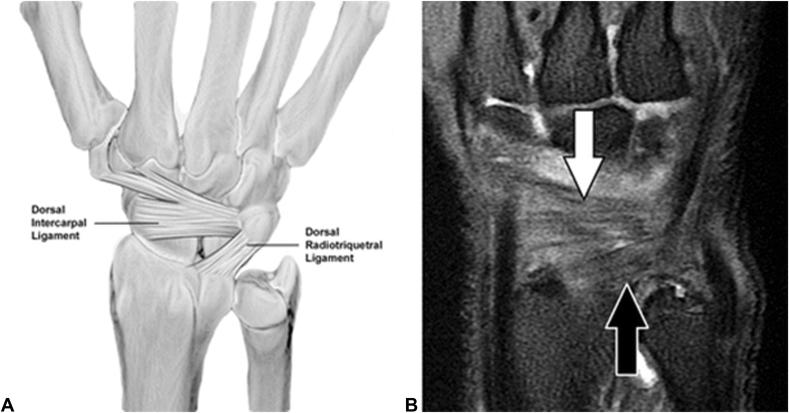

Injuries to the scapholunate interosseous ligament (SLIL) complex can result in a predictable cascade of incongruous motion in the carpus that leads to radiocarpal degeneration. Both acute traumatic impact and repetitive motion can render the SLIL insufficient. A thorough understanding of SLIL anatomy is required for appropriate diagnosis and treatment. Here, we review scapholunate ligament anatomy, prevention strategies, methods of diagnosis, nonoperative and operative treatments, and outcomes. A myriad of treatment options exist for each stage of the SLIL injury, and management should be an open discussion between the patient and physician.

舟月骨间韧带(SLIL)复合体损伤可导致腕骨出现一系列可预测的不协调运动,进而导致桡腕关节退变。急性创伤性撞击和重复性运动均可致使SLIL功能不全。为了进行恰当的诊断和治疗,需要对SLIL的解剖结构有透彻的了解。在此,我们回顾舟月韧带的解剖结构、预防策略、诊断方法、非手术及手术治疗方法以及治疗效果。对于SLIL损伤的每个阶段都有众多治疗选择,治疗方案应是患者与医生之间的充分讨论。